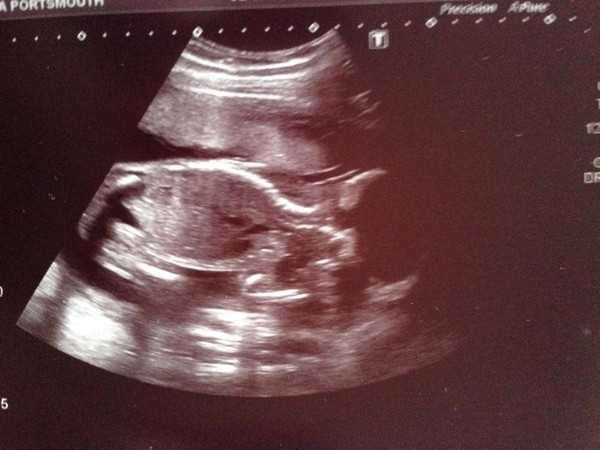

Also in bigger news, we had our scan today one happy healthy baby wriggling so much we couldnt get a decent photo haha

Just back from our scan. Looks like we're having a little girl! Smile